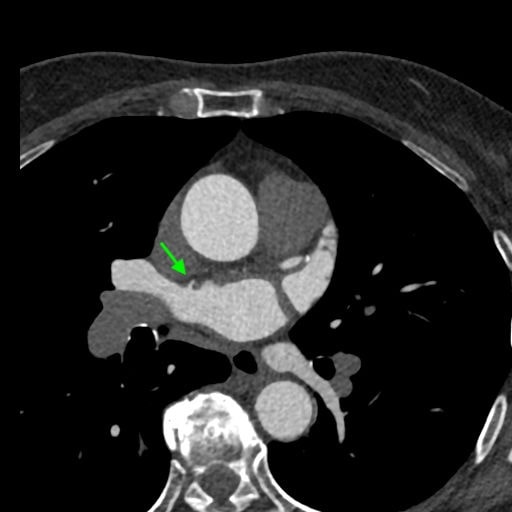

図5.左房から細い血管構造

右上肺静脈の左房開口部腹側から細い血管構造が起始。左房中隔を下降

図6.左房内への造影剤ジェット疑い

造影剤ジェット。左心系は造影され、右心系は造影されてないタイミングで撮影されているため見られる所見。希釈TI法によってタイミング、造影効果が適切に管理されている。